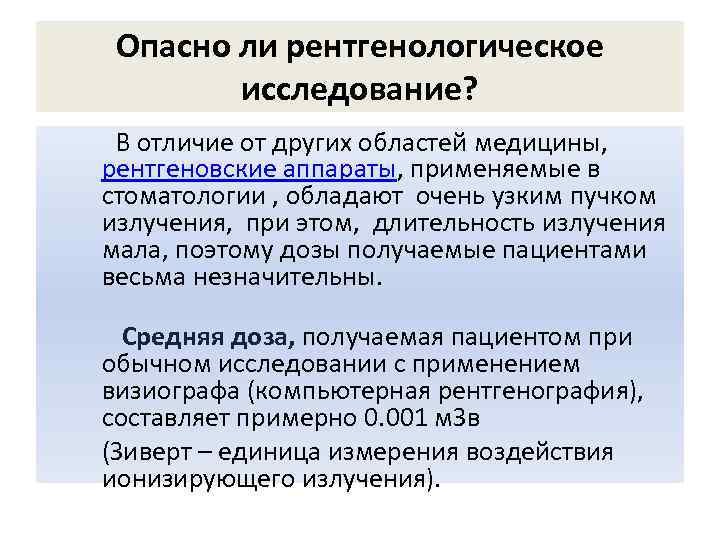

Опасно ли рентгенологическое исследование? В отличие от других областей медицины, рентгеновские аппараты, применяемые в стоматологии , обладают очень узким пучком излучения, при этом, длительность излучения мала, поэтому дозы получаемые пациентами весьма незначительны. Средняя доза, получаемая пациентом при обычном исследовании с применением визиографа (компьютерная рентгенография), составляет примерно 0. 001 м. Зв (Зиверт – единица измерения воздействия ионизирующего излучения).

Опасно ли рентгенологическое исследование? • Доза облучения при панорамном обследовании -0, 02 м. Зв. • В течение года, из внешней среды человек получает облучение (естественный фон) примерно в 3. 0 м. Зв. В • В профилактических (не лечебных целях) годовая доза облучения не должна превышать 1. 0 м. Зв. • Данные цифры и их соотношения легко проанализировать самостоятельно.

Опасно ли рентгенологическое исследование? • В разумных пределах, применение рентгенографического исследования не просто оправдано, а необходимо, при этом, степень нанесения возможного вреда крайне незначительна. • В сети стоматологических клиник очень серьезно относятся к задаче снижения доз радиации для пациента.